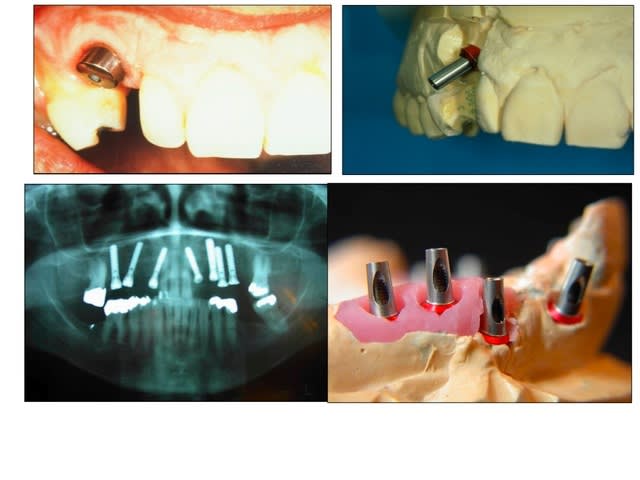

Je pense que la solution tout le monde te l'a donnee , une armature vissee qui te permettra de rattraper les axes. Allez pour te remonter le moral, regardes les photos et dis toi que eux , ils etaient vraiment mal.

Sans titre - Eugenol

ça détend de voir des photos comme ça. Dire que parfois je chipote sur mes cas pour quelques degrés d'angulation...